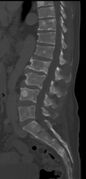

The diagnostic examination of a person with suspected multiple myeloma typically includes a skeletal survey. This is a series of X-rays of the skull, axial skeleton, and proximal long bones. Myeloma activity sometimes appears as "lytic lesions" (with local disappearance of normal bone due to resorption) or as "punched-out lesions" on the skull X-ray ("raindrop skull"). Lesions may also be sclerotic, which is seen as radiodense.[70] Overall, the radiodensity of myeloma is between −30 and 120 Hounsfield units (HU).[71] Magnetic resonance imaging is more sensitive than simple X-rays in the detection of lytic lesions, and may supersede a skeletal survey, especially when vertebral disease is suspected. Occasionally, a CT scan is performed to measure the size of soft-tissue plasmacytomas. Nuclear Medicine Bone scans are typically not of any additional value in the workup of people with myeloma (no new bone formation; lytic lesions not well visualized on nuclear bone scan).

Pathological fracture of the lumbar spine due to multiple myeloma

CT scan of the lower vertebral column in a man with multiple myeloma, showing multiple osteoblastic lesions: These are more radiodense (brighter in this image) than the surrounding cancellous bone, in contrast to osteolytic lesions, which are less radiodense.